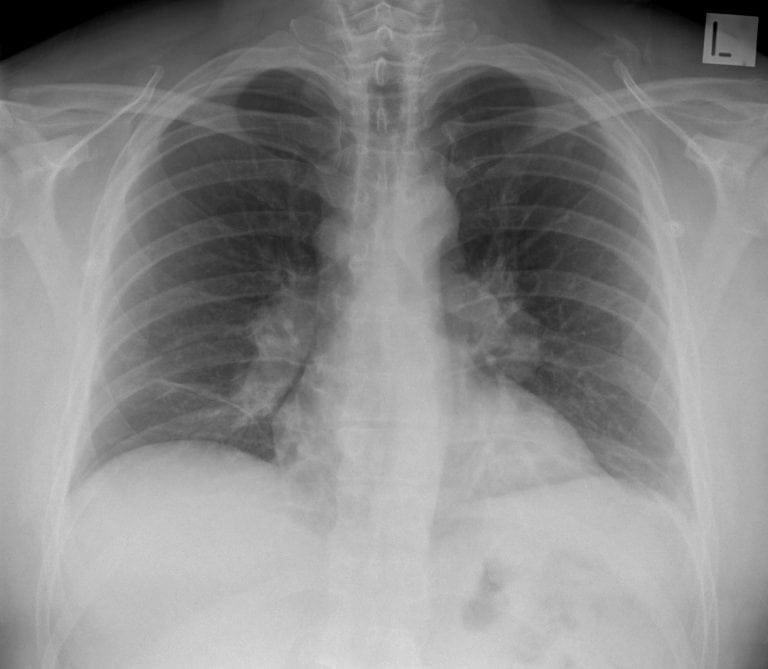

CXR Case 029

A 32 year old old male presents with a dry cough, malaise and arthralgia

Describe and interpret this CXR

There is bilateral hilar adenopathy and bands of atelectasis in both lung bases.

*Lung parenchyma looks normal.

This is sarcoidosis (stage 1 on radiological classification)